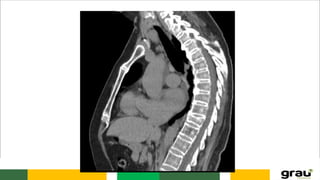

Coluna Vertebral

CURVATURAS: Primárias e secundarias

IMPORTÂNCIA CLINICA: hipercifose, hiperlordose escoliose

IMAGEM PANORÂMICA DA COLUNA !

COLUNA VERTEBRAL CURVATURAS: Primáriase secundarias IMPORTÂNCIA CLINICA: hipercifose, hiperlordose escoliose Caracteristicas das vértebras permitem identificar a que região pertencem.